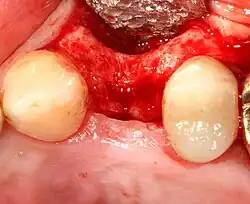

An incision is made across the area and the flap of gingiva is opened to show the bone of the jaw.

An incision is made across the gingiva, and the flap of tissue is reflected to show the bone of the jaw.

A series of slow-speed drills create and gradually enlarge a site in the jaw for the implant to be placed. The hole is called an osteotomy.

Once the bone is exposed, a series of drills create and gradually enlarge a site (called an osteotomy) for the implant to be placed.